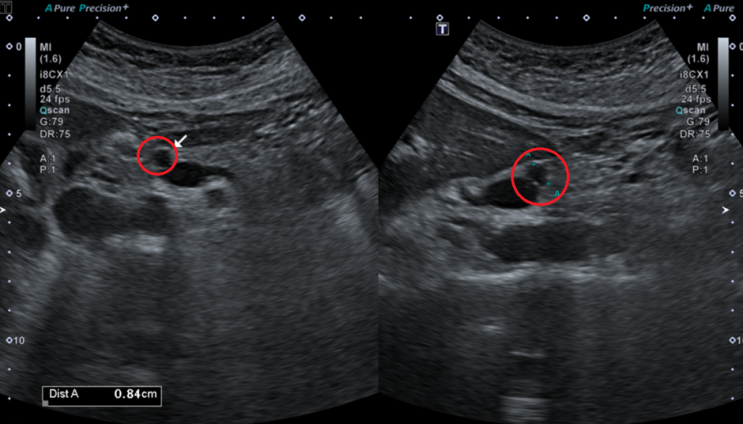

상복부 초음파 상에서 췌장머리쪽으로 8mm크기의 저에코 결절이 보이고 있습니다. 이에 대한 정확한 평가를 위해 추가적으로 췌장 MRI를 시행하였습니다. MRI상 췌장 머리쪽으로 고신호를 가진 8mm크기의 물혹이 관찰됩니다. 이 물혹은 췌관과의 연결성도 보이고 있어, 췌관내유두상점액종양으로 판단되었습니다.

• 췌장MRI: 췌장 머리쪽 8mm 물혹 (빨간 동그라미) 췌장MRI: 췌장 머리쪽 8mm 물혹 (빨간 동그라미)